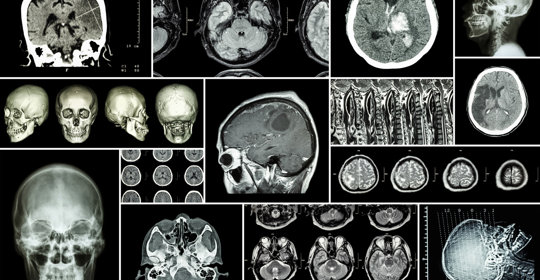

腦出血:CT影像評估與分級分析

本文介紹了如何透過CT影像來評估腦出血的程度以及如何理解腦出血的分級。腦出血CT片子上高密度影反映了出血情況,而腦出血的分級則有助於判斷病情嚴重性和預後。